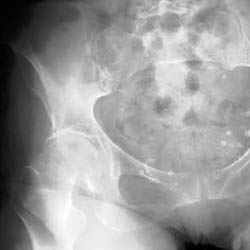

Skeletal Trauma > Pelvis & Hips > Pelvis and Hips Quiz

Pelvis and Hips Quiz

True or False 1. Posterior hip dislocations are less common than anterior. 2. Malgaigne fractures are unstable. | ||||||